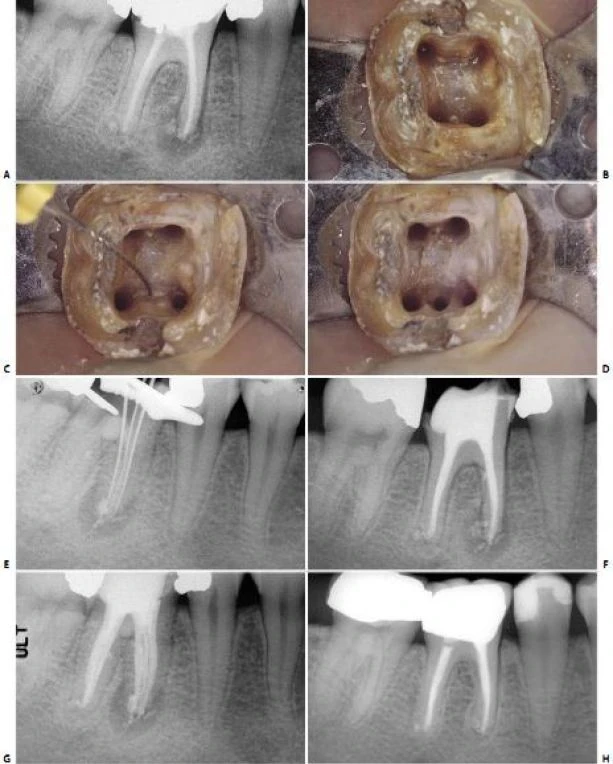

Hình 11.112. Trong một số trường hợp khác, ống tủy gần giữa được thấy ở 1/3 chóp của chân gần.

Hình 11.113. Điều trị lại R46 vì điều trị sót 2 ống tủy: ống xa ngoài và ống gần giữa. A. Phim trước điều trị. B. Xoang tủy sau khi bộc lộ 4 ống tủy. Chú ý sự hiện diện của 1 chỗ lõm ở vùng eo giữa 2 chân gần. C. Một file số 10 đi vào chỗ lõm và  rất dễ dàng đi vào ống tủy gần giữa, ống này có một lỗ chóp riêng. D. Xoang tủy sau khi sửa soạn 5 ống tủy E. Ba file chỉ ra rằng có 3 ống tủy riêng biệt ở chân gần  F. Phim sau điều trị. G. Một góc chụp khác cho thấy hình ảnh 5 ống tủy. H. 7 năm sau điều trị, tổn thương lành hoàn toàn.

Thương tổn trước đây không phải do vật liệu trám ra ngoài mà vì vi khuẩn còn lại trong ống tủy bị bỏ sót.